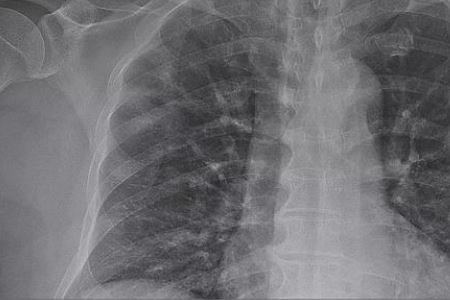

据报道,截至当地时间12日上午10时30分,日本共确诊新冠肺炎病例638例。这些感染者包括日本国内的感染者和游客等624人,以及乘坐日本政府包机回到日本国内的14人。确诊病例中包括15例死亡病例。另据报道,此前停靠在日本横滨港的“钻石公主”号邮轮上,确诊新冠肺炎的乘客和乘务人员共696人,包括7例死亡病例。

另外,据日本放送协会(NHK)报道,当地时间12日上午,日本兵库县姬路市政府发布消息称,该市新增4例新冠肺炎确诊病例。报道称,被确诊的4人均为女性,年龄从50多岁到80多岁不等。据介绍,这4人中,1人在11日出现发热症状,其他3人目前还没有出现症状。目前,兵库县的新冠肺炎确诊病例已增至41例。(备注:信息来源“中国新闻网”。)